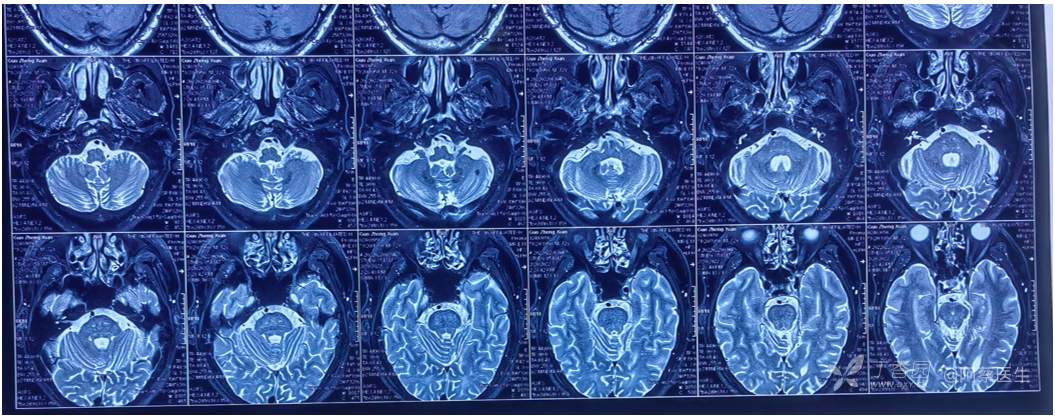

外院内耳MRI(第一次手术前)

MR:左侧舌咽神经明显受血管压迫(小脑后下动脉),三叉神经是否存在血管压迫显示不清(医师自己阅片)